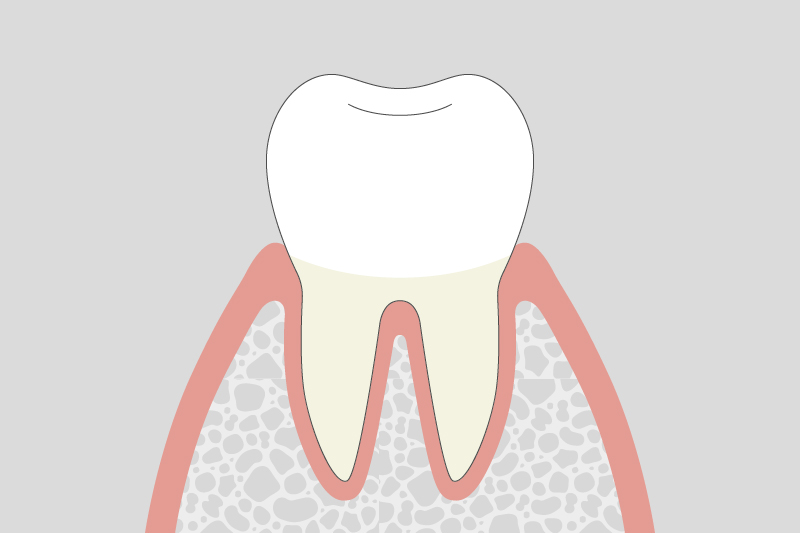

01.

歯肉炎(軽度)

歯ぐきが赤く腫れ、歯磨きの際に出血しやすくなります。まだ歯を支える骨への影響は少ない段階です。